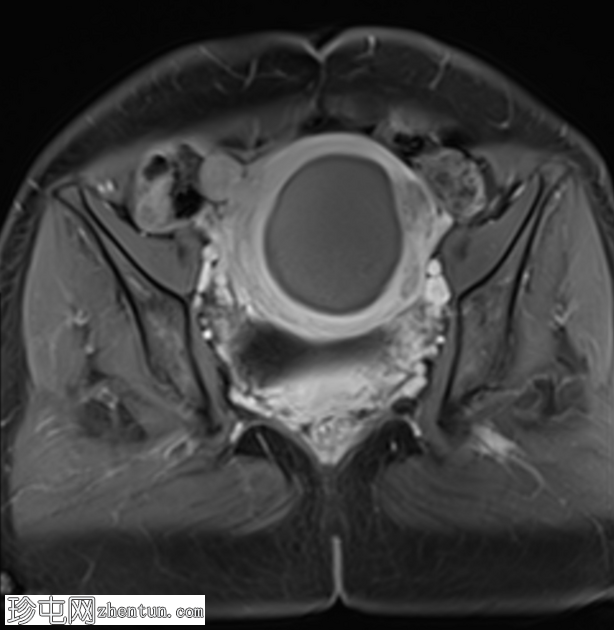

矢状位

T2加权像

子宫前壁可见一边界清晰的壁内病灶,大小约7.8 × 7 × 6.8 cm。脂肪抑制T1加权像呈弥漫性高信号,T2加权像呈高信号伴低信号环,无扩散受限及对比增强。

此外,可见一个2厘米的带蒂浆膜下肌瘤,以及较小的肌壁内和浆膜下肌瘤;所有肌瘤均呈均匀强化。

盆腔内可见少量游离液体,可能为生理性。